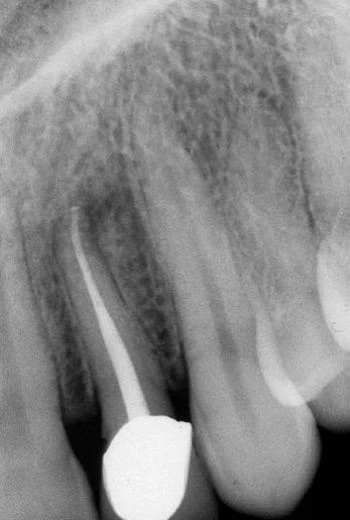

Hình 5.41. A. Phim X-quang trước điều trị của răng cửa giữa hàm trên bên phải. Lỗ chóp nằm trên cùng một mặt phẳng trên đường đi của tia X: nó có thể đối diện với mặt trong hoặc mặt ngoài. B. Phim X-quang thứ hai chụp theo hướng gần-xa cho thấy đoạn cong đối diện với mặt ngoài. Việc điều trị tủy được hoàn tất, giữ nguyên góc chụp cho phép nhìn thấy được điểm cuối cùng trên X-quang của ống tủy. C. Phim sau điều trị. Lưu ý rằng chỉ với góc chụp này mới thấy được hình ảnh tổn thương nhỏ tại chóp chân răng. D. Phim sau điều trị được chụp theo tiêu chuẩn hình chiếu. Lưu ý rằng vật liệu trám ống tủy dường như bị ngắn đi chừng 2mm và tổn thương cũng đã lành.